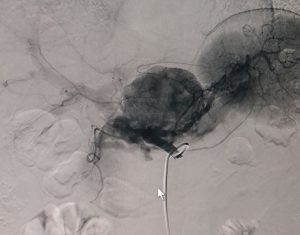

BVXA – BỆNH HIẾM: RÒ MẠCH TỤY SANG TĨNH MẠCH, ĐIỀU TRỊ THÀNH CÔNG BẰNG CAN THIỆP MẠCH MÁU DƯỚI DSA.

Ngày 08/6/2017, các bác sĩ hai chuyên khoa Ngoại Tổng Quát và Trung tâm Can thiệp Tim Mạch tại BVXA đã phối hợp can thiệp điều trị thành công cho bệnh nhân V.T.T. (sinh năm 1962, ngụ tại Huyện Hòa Thành, Tỉnh Tây Ninh) bị dò động mạch tụy lưng vào tĩnh mạch cửa. Đây […]